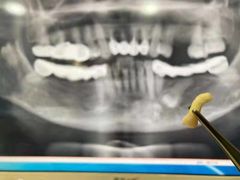

• 牙易美口腔(圣堂店)

• -牙易美口腔(圣堂店)

胡闹_1999 | 21-04-26